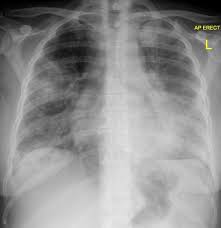

Portail des communes de france : En cas de doute diagnostique, l'angioscanner thoracique permet d'éliminer l'embolie pulmonaire. Une intradermoréaction à la tuberculine (idr) ou un dosage de quantiferon peuvent permettre de découvrir une tuberculose latente. Nos coups de coeur sur les routes de france. 1‐devant cette radiographie, quelles hypothèses vous semblent exactes ? Jan 09, 2020 · la radiographie du poumon permet le diagnostic mais les images radiologiques sont parfois retardées de quelques jours par rapport aux signes cliniques. Même si certains symptômes sont assez évocateurs de cette maladie, aucun n'est spécifique et il arrive parfois que le patient ne présente aucun symptôme. Radiographie du thorax de face et de profil;

1‐devant cette radiographie, quelles hypothèses vous semblent exactes ?

Antigène urinaire du streptoccocus pneumoniae. Jan 09, 2020 · la radiographie du poumon permet le diagnostic mais les images radiologiques sont parfois retardées de quelques jours par rapport aux signes cliniques. Nos coups de coeur sur les routes de france. Radiographie du thorax de face et de profil; Jun 25, 2021 · les informations sur le médicament humira 40 mg/0,4 ml sol inj en stylo prérempli sur vidal : A‐pneumonie franche lobaire aiguë b‐infection à pneumocoque c‐légionellose d‐oedème aigu du poumon e‐infarctus sur embolie pulmonaire Dec 24, 2019 · diagnostic : 1‐devant cette radiographie, quelles hypothèses vous semblent exactes ?